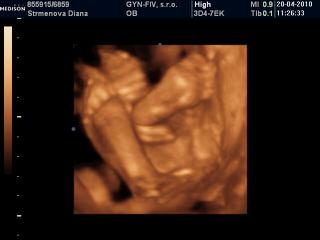

Kamajka tak vidis, nakoniec to ufonik urcite nebude 😉 ja koncim 25tt a zajtra idem na 3D tak aspon uvidis ake foto to budu.

ja som bola na 3D v 22tt a uz maleho bolo krasne vidiet uz bol taky pekny babatkovsky ziadny Ufonik 🙂 ale kedze nechcel ukazat tvaricku tak mi doki v ramci ceny spravi znova 3D na poradni a to budem v 27tt 😉 a moj doktor robi aj take 3D ze vsetko skontroluje pozrie poukazuje da fotku a zaplati sa len 10eur ale je to bez DVD-cka, ale mam stastie ze maly sa nechcel ukazat tak to budem mat zadarmo a aspon ho zase uvidim stuplika maleho ze ako narastol 😵

ahojte...didulka, krasne zabery, mala je nadherna 😵

Didulka kraaaaaaaaaaaaaasa, uz nech je zajtra a ja mam take iste krasne fotecky 😉